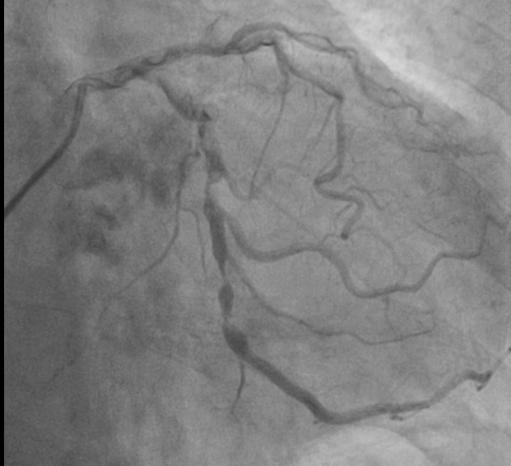

术中,在DSA(数字减影血管造影)严密实时监测下,何晋主任医师从杨爷爷大腿根部股动脉穿刺,通过大血管将主动脉支架瓣膜及装置输送到病变的主动脉瓣位置,缓缓释放支架瓣膜,经过精密调控,支架瓣膜精确植入,原先狭窄的瓣膜口子一下就开通了,术中监测主动脉瓣和心室压差为零。